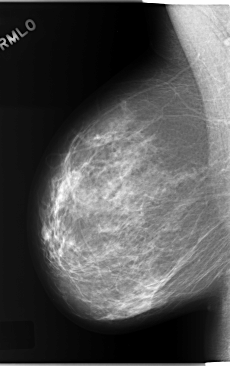

C_0207_1.RIGHT_MLO

RIGHT_MLO LINES 5856 PIXELS_PER_LINE 3672 BITS_PER_PIXEL 12 RESOLUTION 50 NON_OVERLAY